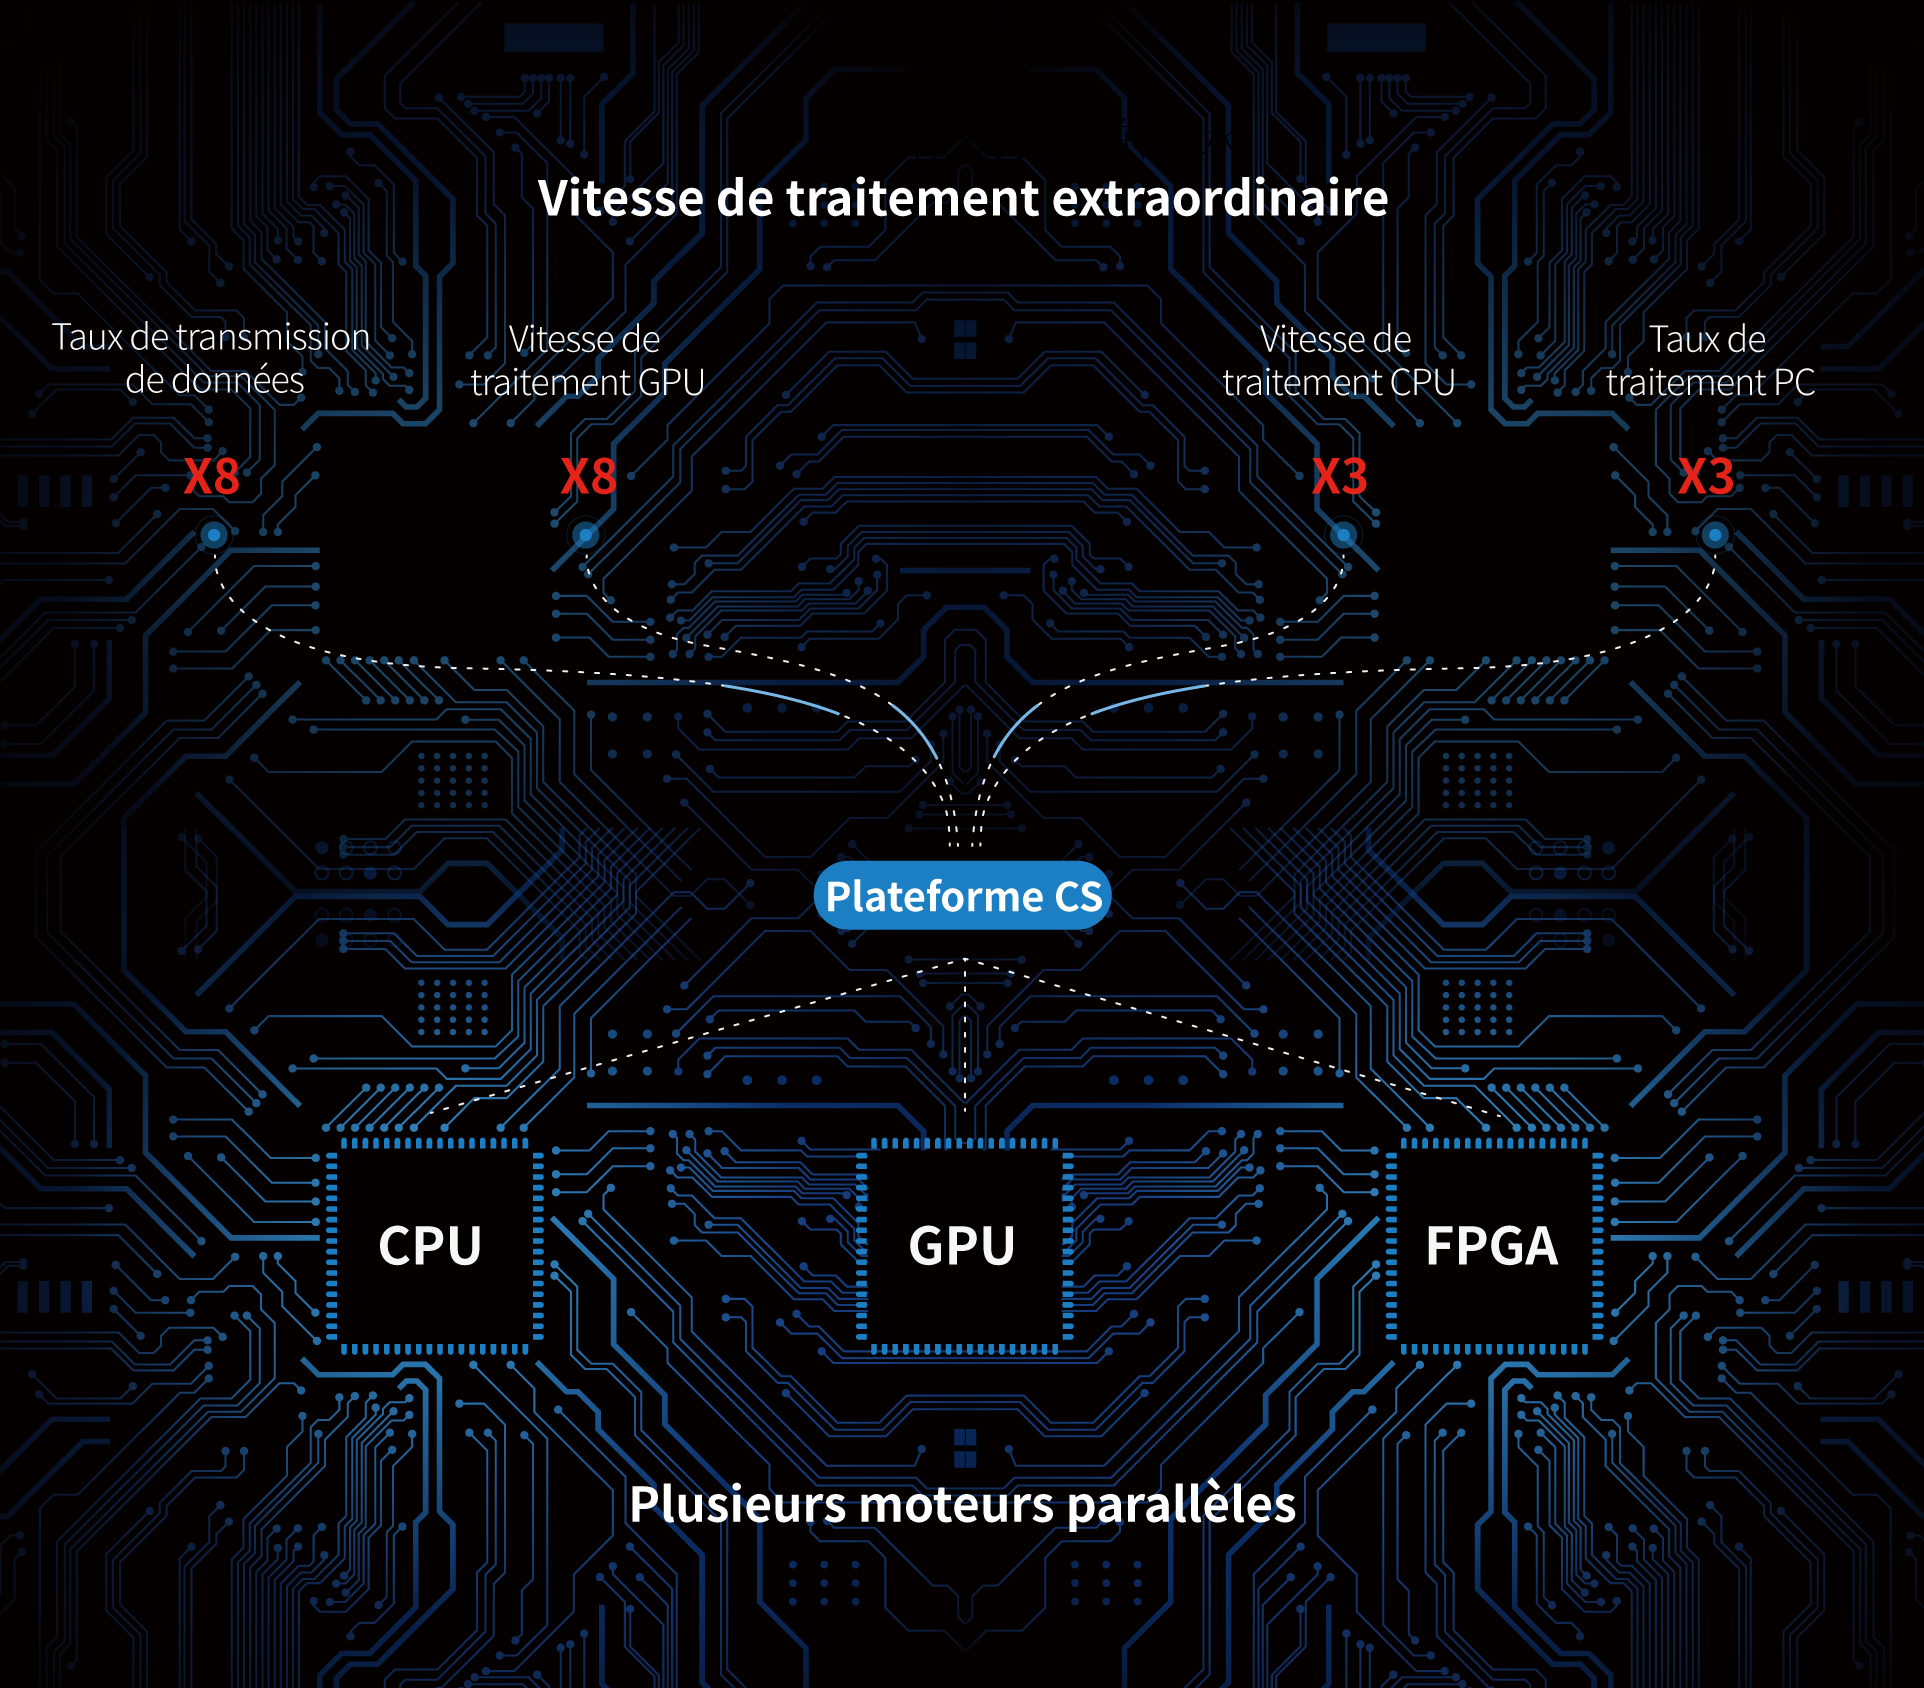

Plateforme CS de pointe dotée d'une technologie d'imagerie super-résolution unique dans l'industrie